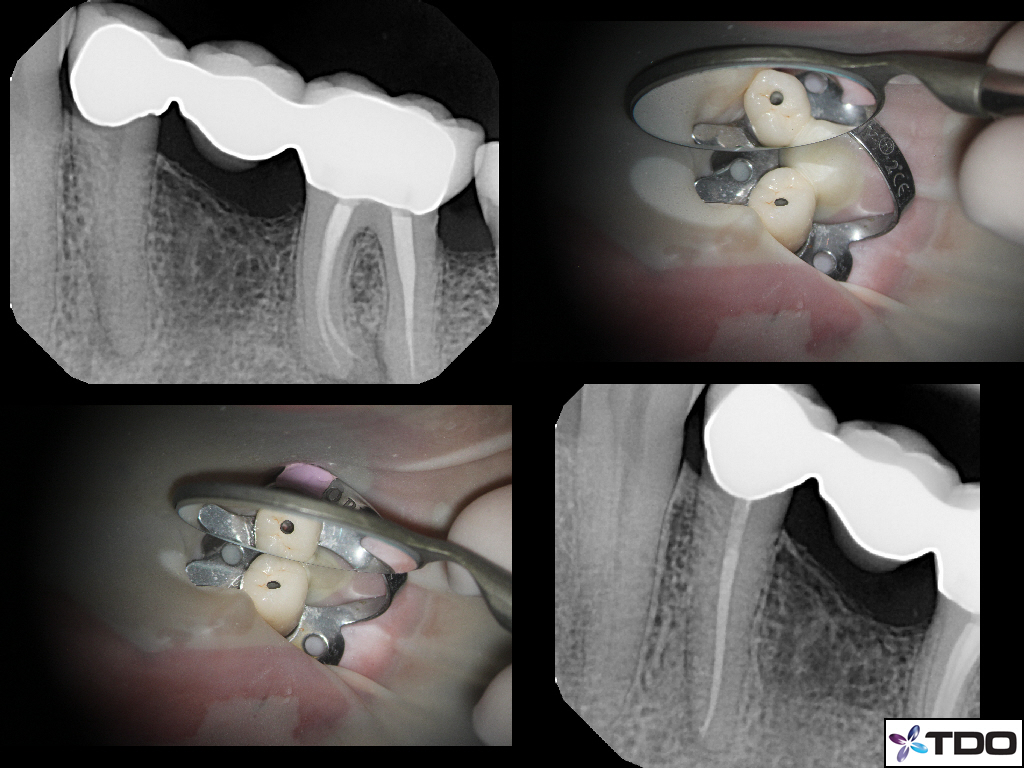

Beautiful work Pushpak. How many of these were X-Nav?